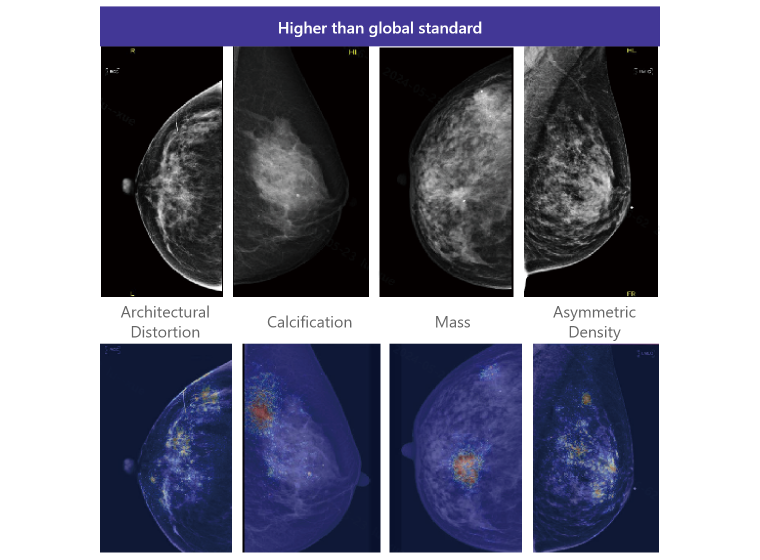

Our system assists doctors in diagnosing, particularly for

breast diseases. It can precisely identifies structural

lesions and calcifications in the breast, providing

AI-assisted diagnosis results with an AUC of 0.902, far

exceeding global standards.